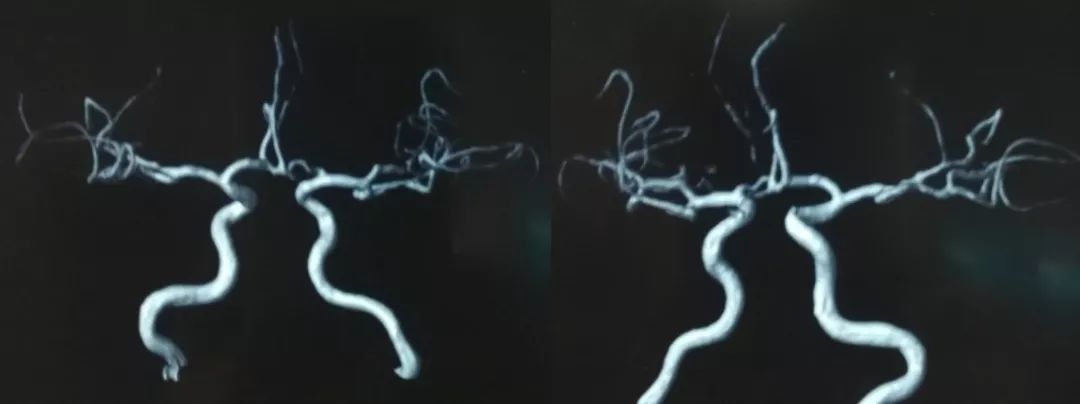

1、局麻后右侧股动脉穿刺置入6F动脉鞘,泥鳅导丝导引下6F导管超选至左侧颈内动脉起始段,造影示左侧颈内动脉C1段夹层动脉瘤。因我院机器未安装三维测试,运用圆规和尺子测量,得出血管直径10.5 mm,6F导引导管直径0.45 mm,6F导引导管实际管腔直径2.12 mm,根据公式计算2.12/0.45=X/10.5 X=4.946 mm ;考虑血管实际直径约5.0 mm,因此选择5.5 mm*35 mm Tubridge支架(图4)。

3、术后造影显示Tubridge支架位置良好,动脉晚期瘤内造影剂滞留明显(图6 )。

图6

1、动脉瘤位于左侧颈内动脉C1段,具有夹层动脉瘤特征,患者有中风病史考虑与夹层血栓脱落有关,病例临床中比较少见。

2、由于动脉瘤位于颈内动脉C1段远端,外科手术视野刁钻,外科治疗困难风险增大。应用覆膜支架或颈内动脉支架-Wallstent支架到位困难,或即使到位后释放困难,且影响患者的生活质量。

3、根据经验Tubridge支架术中短缩率较高且有较高的径向支撑力,支架选择的要求较高。根据载瘤动脉直径为4.946 mm,选择5.5 mm的血流导向装置。